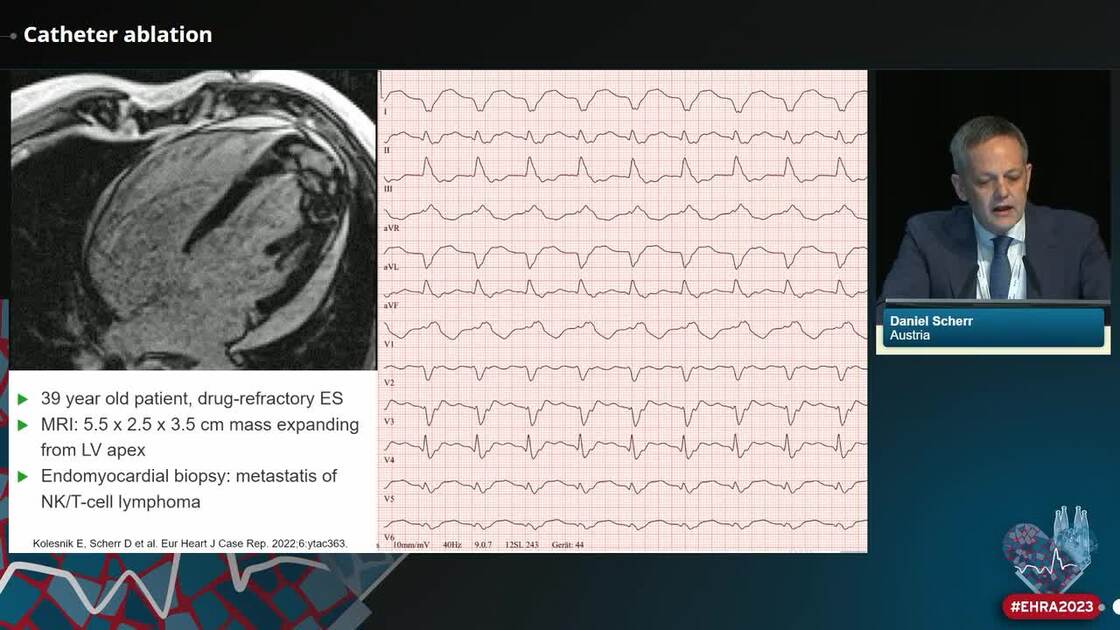

ESC 365 Epicardial catheter ablation in a patient with symptomatic Esc Guidelines Catheter Ablation The european society of cardiology (esc) provides clinical practice guidelines for patients with atrial fibrillation (af), based on the. A joint expert consensus statement on catheter and surgical ablation of atrial fibrillation (af) by four cardiac electrophysiology societies. Ehra, a branch of the esc, publishes international standards for treating atrial fibrillation with catheter or surgical ablation. Overall, the 2020 esc. Esc Guidelines Catheter Ablation.